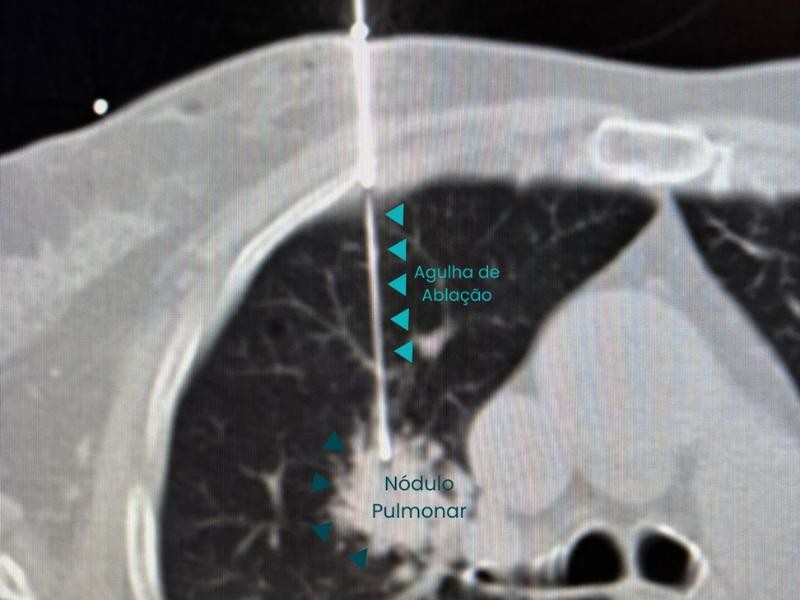

Conquistou o primeiro lugar no exame nacional da SOBRICE e se destaca em procedimentos minimamente invasivos, como ablação de tumores e biópsias guiadas. Atende nos melhores hospitais de São Paulo, incluindo o Hospital Nove de Julho e Vila Nova Star.